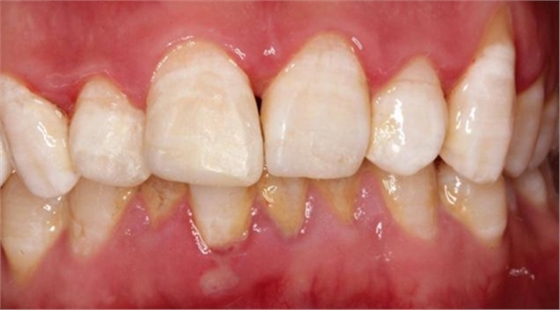

術(shù)后即刻如下圖:

術(shù)后5小時(shí)復(fù)查如下圖: